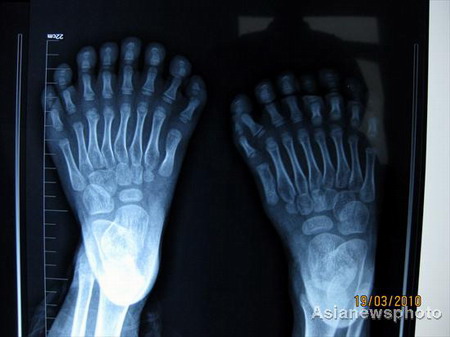

An X-ray of the feet of the 6-year-old boy who has a total of 31 fingers and toes, which outnumber the current world record of 25.[Photo/Asianewsphoto]